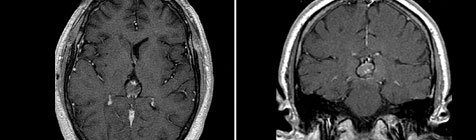

Следующим звеном в диагностике герминомы головного мозга является применение КТ и МРТ головного мозга. Томографические методы исследования позволяют установить опухолевый характер образования, его размеры и расположение. Примерно у 40% больных с герминомой головного мозга выявляется характерный для этой опухоли признак - опухолевая инфильтрация зрительных бугров и наличие расположенного в середине петрификата (симптом бабочки). В пользу герминомы могут говорить распространение опухолевого процесса по боковым желудочкам и метастазирование в инфундибулярную область III желудочка.